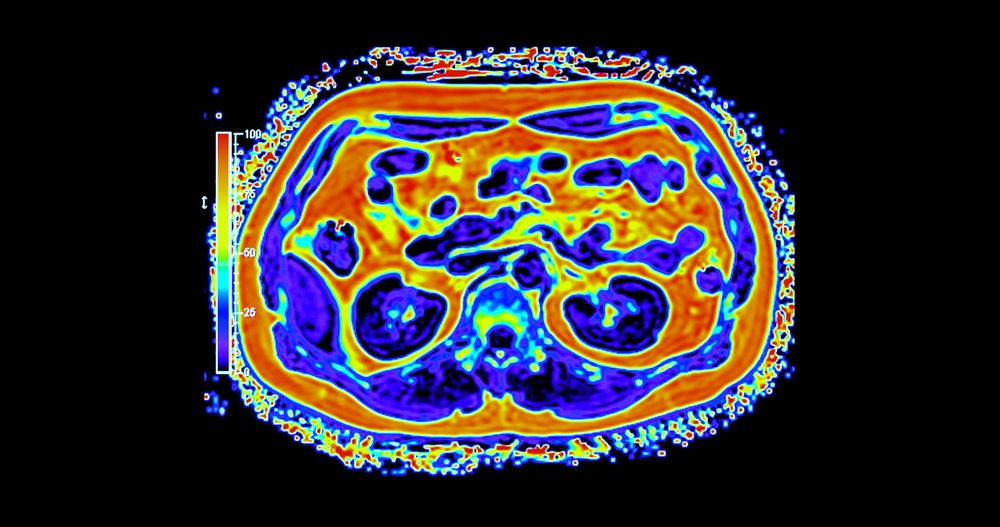

Nustatant vėžio išplitimą gali būti taikomas vienas arba keli šie diagnostiniai tyrimai:

• Radiologiniai tyrimai: kompiuterinė tomografija (KT), magnetinio rezonanso tomografija (MRT), pozitronų emisijos tomografija (PET), rentgenograma,